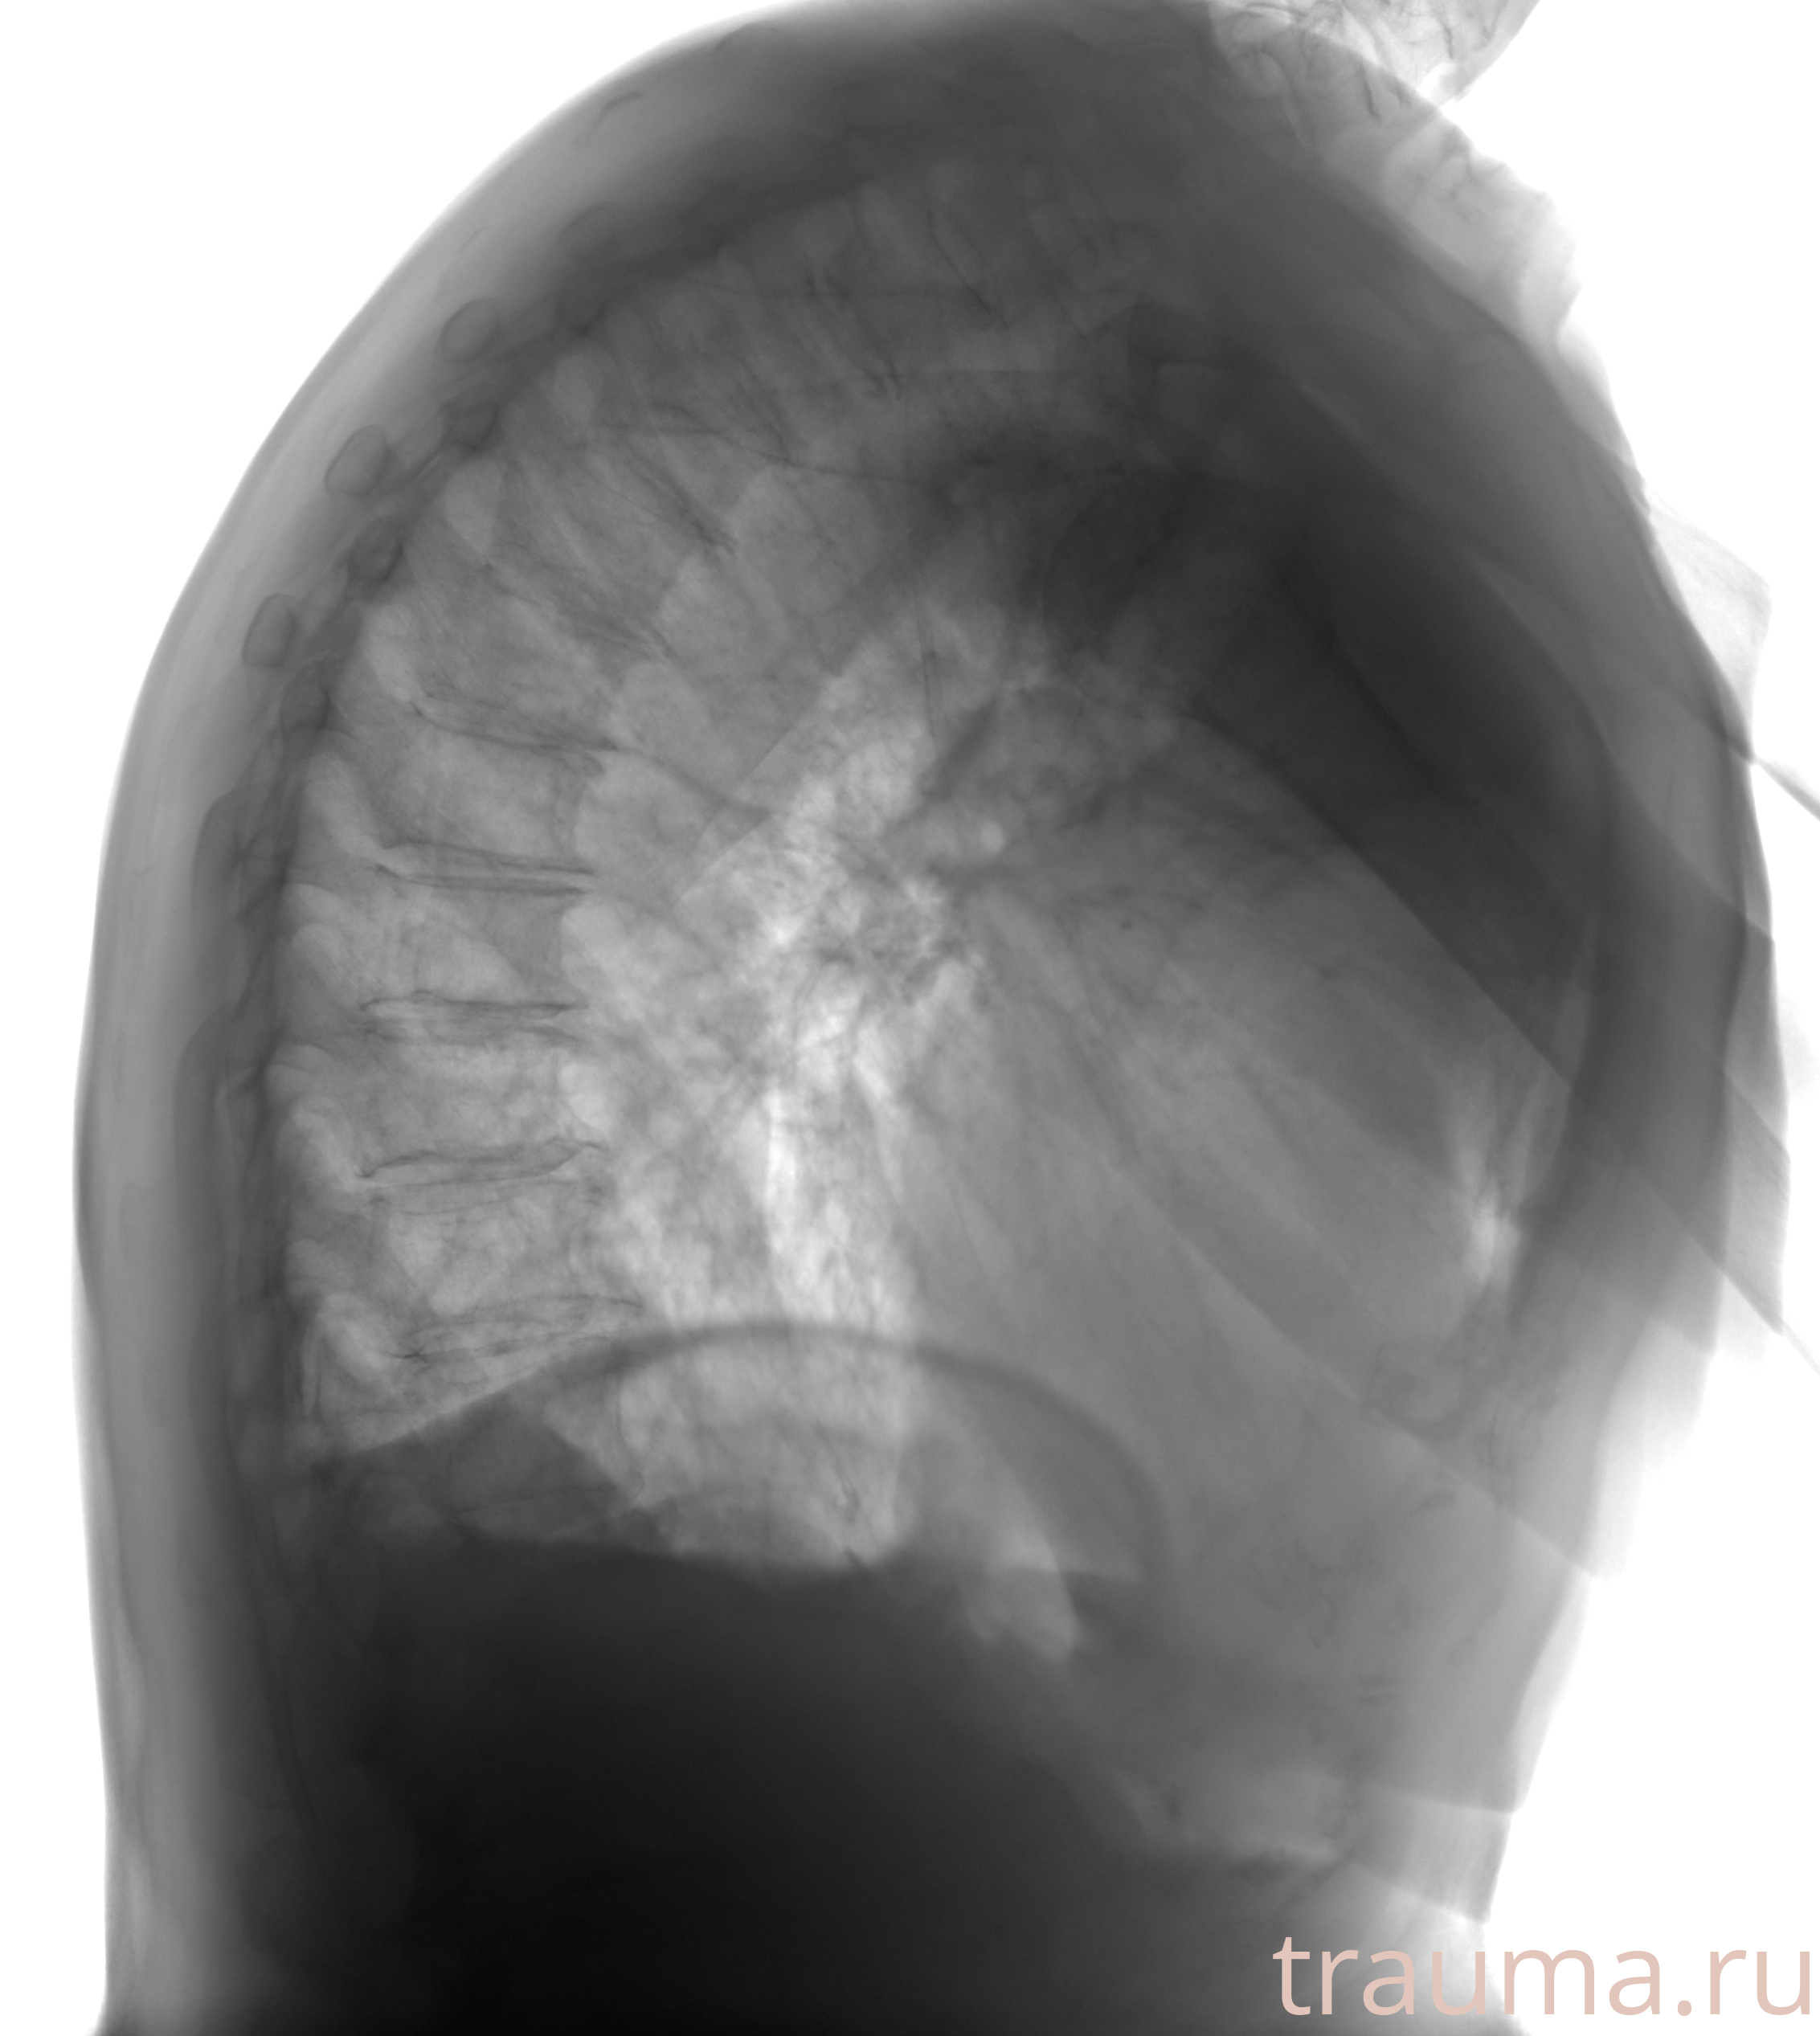

Рентгенограммы

Рентген на дому: по вашему адресу приезжает врач-рентгенолог, травматолог-ортопед с мобильным рентгеновским аппаратом, проводит диагностику травмы или заболевания, делает необходимые рентгенограммы, дает рекомендации по дальнейшему лечению. Получить качественные снимки в домашних условиях возможно благодаря уникальной методике, разработанной МосРентген Центром для института  Склифосовского

при переломе шейки бедра и пневмонии от компании МосРентген Центр - партнера Института имени Склифосовского